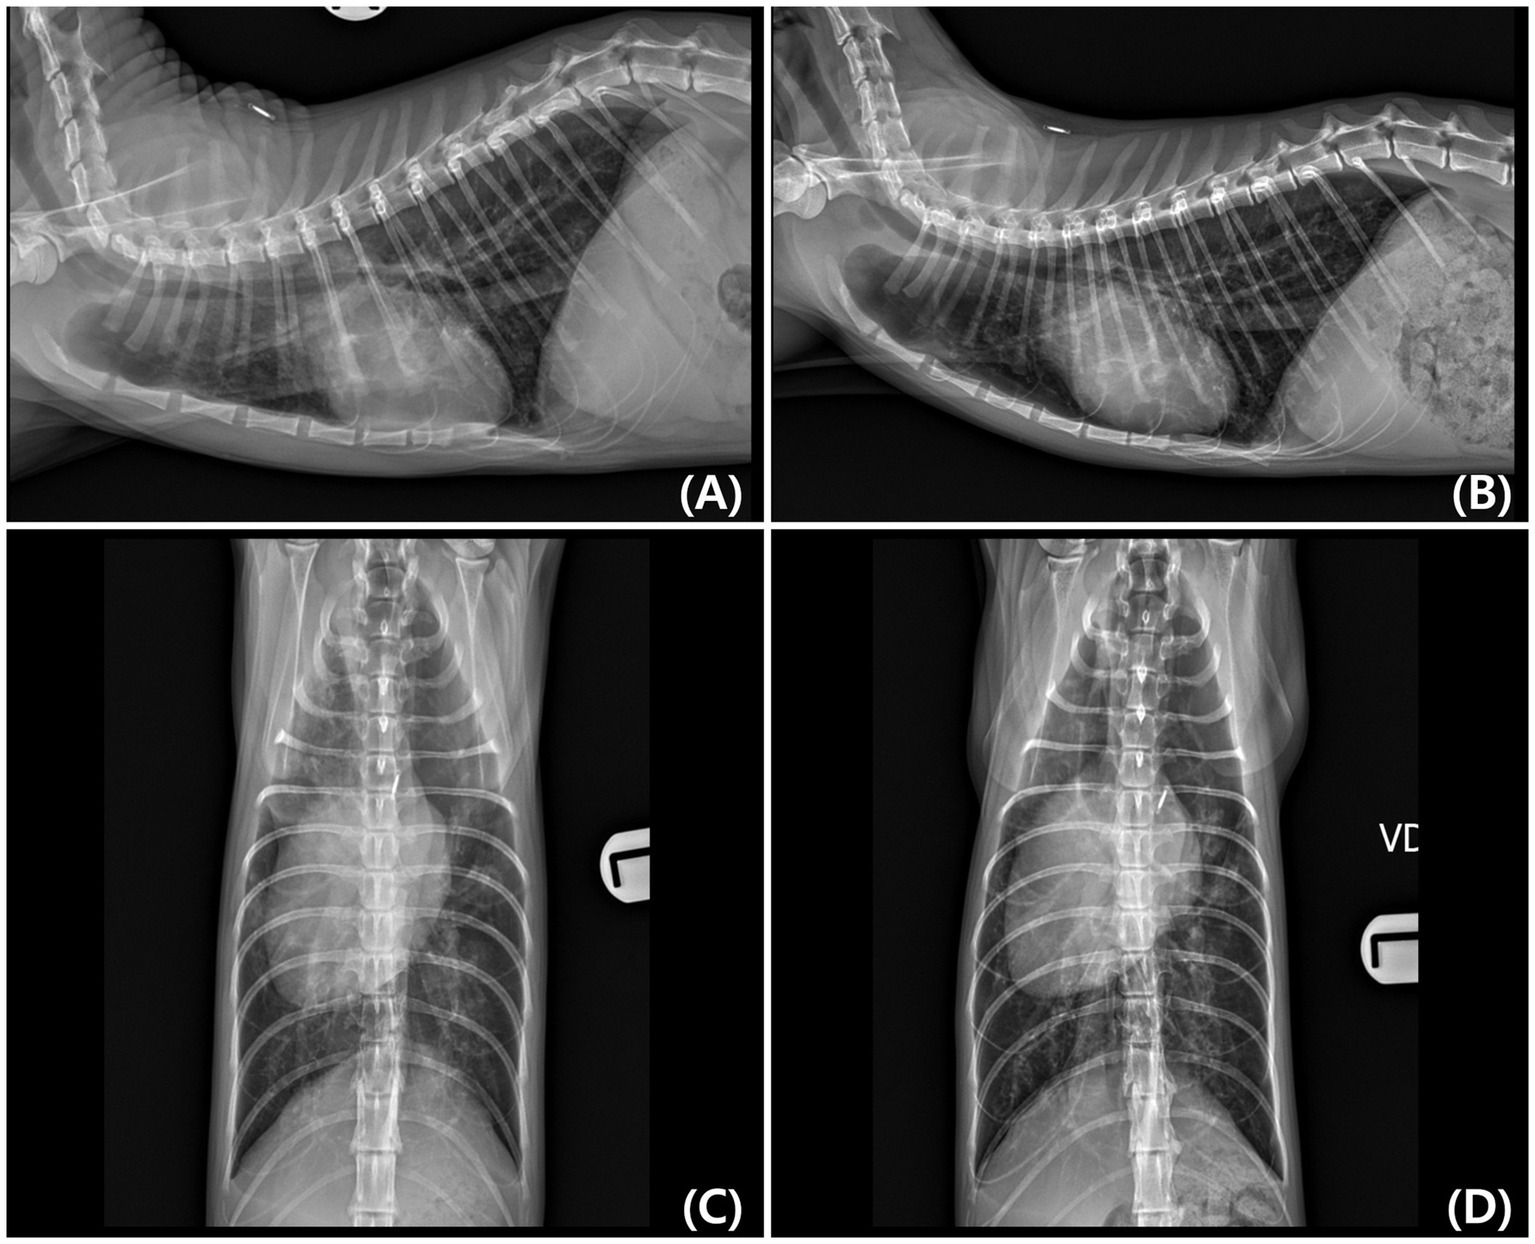

Concurrent atrial septal defect (ASD) and ventricular septal defect (VSD) are rare in cats. A 7-month-old intact female Sphynx cat was presented for evaluation of respiratory distress and exercise intolerance. Thoracic radiographs showed generalized cardiomegaly and pulmonary infiltrates, consistent with cardiogenic pulmonary edema. Transthoracic echocardiography revealed an ostium secundum–type ASD and a perimembranous VSD, with structurally normal atrioventricular valves and annuli. These features supported the diagnosis of concurrent ASD and VSD, rather than an atrioventricular septal defect. Color Doppler echocardiography and agitated saline contrast studies confirmed bidirectional shunting at both defect sites. Additionally, echocardiographic findings were consistent with pulmonary hypertension. As Eisenmenger syndrome was suspected and the owner declined invasive intervention, surgical repair was not performed. Initial treatment with furosemide and supplemental oxygen led to clinical improvement. The owner later discontinued diuretics; however, the cat remained asymptomatic for several months. Cyanosis and erythrocytosis developed approximately 8 months after initial presentation. Follow-up thoracic imaging and Doppler echocardiography demonstrated reduced cardiac silhouette size without recurrent pulmonary edema, right-sided chamber enlargement with right ventricular hypertrophy, and decreased pulmonary-to-systemic flow ratio, consistent with progression of Eisenmenger physiology. Medical management with phlebotomy, sildenafil, clopidogrel, and oxygen supplementation provided temporary stabilization; however, the cat eventually died approximately 1 year after diagnosis, likely due to disease progression and inconsistent therapeutic compliance. Postmortem examination confirmed both septal defects and marked right ventricular hypertrophy, consistent with the ante-mortem imaging findings. Histopathological examination revealed pulmonary vascular remodeling and myocardial fibrosis, indicative of chronic pulmonary hypertension. This report represents the first documented case of concurrent ASD and VSD with Eisenmenger physiology in a cat, with long-term clinical follow-up and postmortem confirmation.